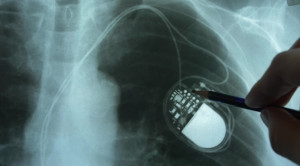

• Pacu Jantung Biventrikular vs Ventrikular Kanan untuk AV Blok Simtomatik – Telaah Jurnal Alomedika

Pacu Jantung Biventrikular vs Ventrikular Kanan untuk AV Blok Simtomatik – Telaah Jurnal Alomedika

Biventricular vs Right Ventricular Pacing Devices in Patients Anticipated to Require Frequent Ventricular Pacing (Biopace). Funck RC, Müller HH, Lunati M, et...(Baca Selengkapnya)